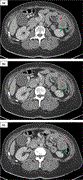

A case of laparoscopic anterior resection for rectal cancer with duplication of the inferior vena cava using preoperative 3D computed tomography angiography

Akinobu Furutani and others

Journal of Surgical Case Reports, Volume 2020, Issue 9, September 2020, rjaa223, https://doi.org/10.1093/jscr/rjaa223